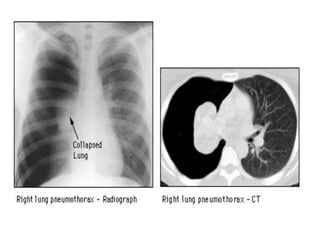

RADIOGRAPHICDIAGNOSIS

1- CXR

The standard procedure in making the diagnosis.

 It should be upright and preferably in the posteroanterior

projection. It is possible to miss a pneumothorax in a

semisupine portable anteroposterior view. If the patient

cannot be upright, a lateral decubitus view with the suspect

side positioned up may be helpful.

 A giant bulla can mimic a pneumothorax. Subtle lines demarcate

a bulla, which tends to be surrounded by thickened visceral pleura.

In addition, a pleural line can frequently be seen with lung

markings visible beyond the suspected bulla (double wall sign)

2- CT CHEST

 CT is seldom required for routine diagnosis of SP

 it can help differentiate between SP and a giant bulla.

 Controversy exists about the significance of routine chest CT to evaluate

for subpleural blebs. However identification of large or multiple subpleural

blebs on CT is an indication for early surgical intervention to prevent

recurrence.